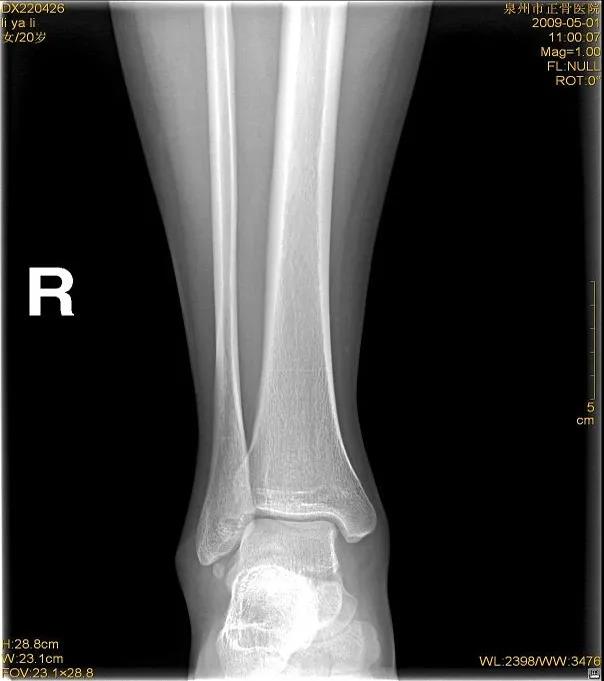

X线

踝关节正位

踝关节侧位